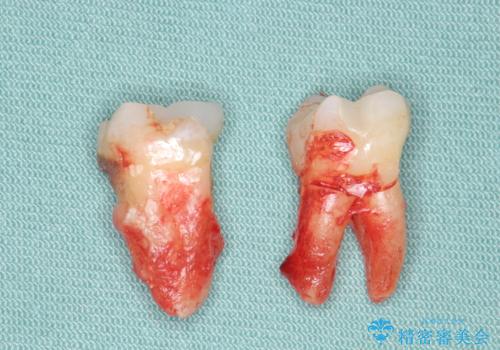

- 歯周病が進行し、根尖付近まで歯槽骨(歯を支える骨)の吸収が見られる歯の治療を希望され来院されました。

長期的な予後の見込めない奥歯の抜去を行い、骨と歯ぐきの治癒を待ち、インプラント治療を計画します。